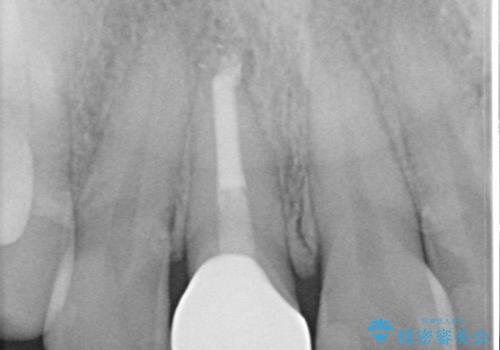

- 前歯のガタつき、変色を主訴に来院された患者様です。術前診査のCT撮影にて、変色した前歯の根の先に病巣があることが判明しました。そこで、マウスピースによる矯正治療と、前歯の根管治療、かぶせ物のやり直し治療を並行して行いました。